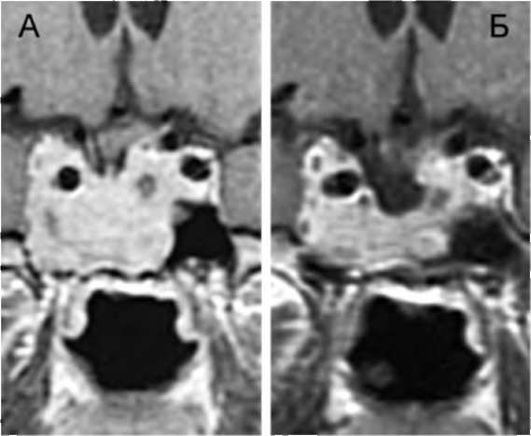

• МРТ и КТ головного мозга: спинномозговая жидкость определяется в полости седла; гипофиз обычно сдвинут к задней или нижней стенке седла, его вертикальный размер менее 3 мм.

Помимо основных изменений в хиазмально-селлярной области, МРТ позволяет выявить косвенные признаки внутричерепной гипертензии, сопутствующие этой патологии, - расширение желудочков и ликворосодержащих пространств.